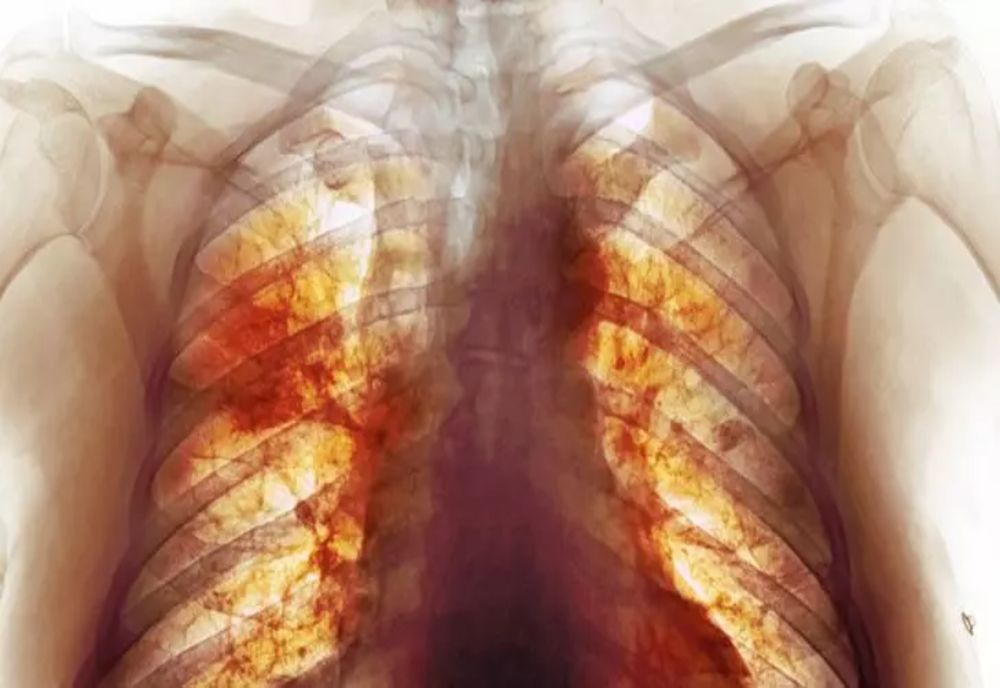

Național Geographic a publicat o radiografie făcută la cel mai mare și performant computer tomograf - HiP-CT scan.

În imagine se vede impactul virusului Covid asupra plămânului unui pacient în vârstă de 54 de ani - vasele de sânge active sunt roșii, cele blocate sunt galbene și spațiile aeriene sunt colorate cu cyan (albastru-verzui). IMAGINEA POATE FI VĂZUTĂ AICI.

"Pentru prima dată în istoria medicinei, putem vedea cum arată un plămân trecut prin infecția cu coronavirus", a declarat Claire Walsh, profesor doctor în cadrul UCL (University College London).

Cu ajutorul computerului tomograf HiP, cercetătorii au putut observa adevărata dimensiune a dezastrului provocat de infecția cu coronavirus. Computerul tomograf permitea vizualizarea celor mai mici vase de sânge și chiar a celulelor.

Tehnica face posibilă realizarea unor imagini fidele a modului în care virusul Covid afectează organele interne. În plus, se poate vedea felul în care vasele de sânge din plămânii afectați sunt redesenate de boală.